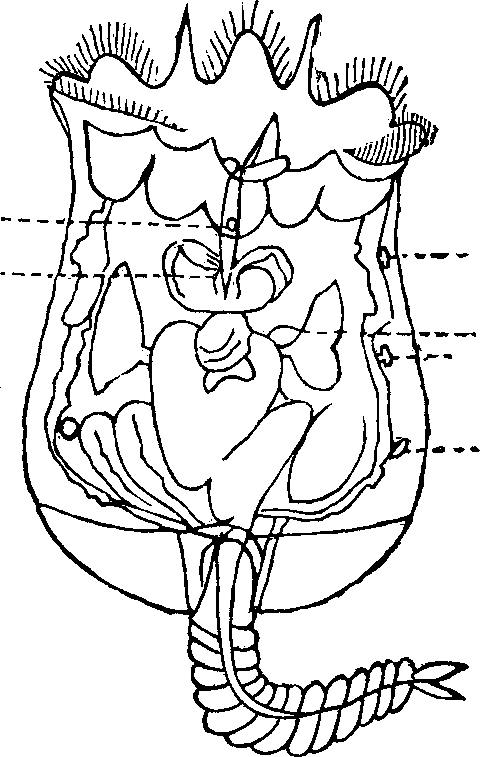

Fig. 28. A representation of the

interior of the stomach. 1. The esophagus. 2. Cardiac orifice

opening into the stomach. 6. The middle or muscular coat. 7.

The interior or mucous coat. 10. The beginning of the duodenum.

11. The pyloric orifice.